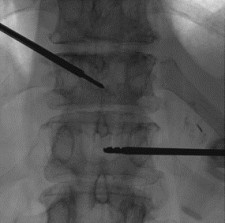

Vertebral body tumor access

AveCure® microwave ablation system is successfully used to treat and relieve pain from metastatic vertebral-body tumors and bone cement is used to fill the remaining cavity to restore the mechanical structure. The procedure is minimally invasive. A bone cannula is inserted through a skin incision to access the tumor and the patient is left with a small hole in the skin, which quickly heals with almost no scar after the procedure. The AveCure® ​system utilizes a smart antenna in either probe or catheter format and a microwave energy controller to select the correct size, temperature and timer settings appropriate for safe, effective and predictable treatment.